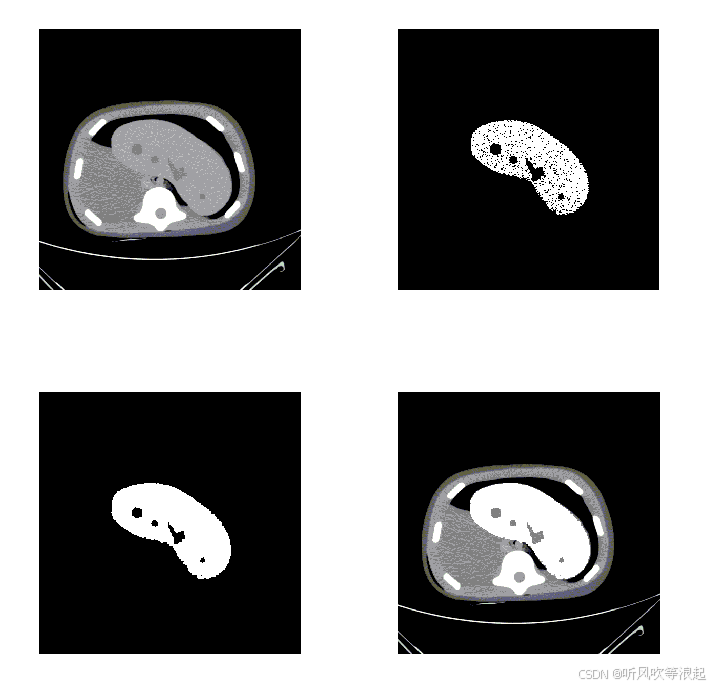

- 适配任务:细粒度图像分类(如花卉、鸟类识别)、医学图像分割(如细胞、器官边界)。

- 适配任务:医学图像分割(如MRI器官分割)、遥感图像分类(如土地覆盖分类)。

- 实验增益:在BraTS 2021 MRI分割中,Dice系数提升3.3%;在EuroSAT遥感分类中,准确率提升2.8%。

- 医疗影像:病灶分割(如肿瘤、器官)、疾病诊断(如X光、MRI)。